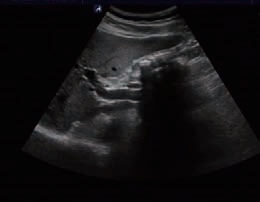

3)胆囊泥沙样结石。泥沙样结石沉积在胆囊最低位置,呈层状分布的高回声带,后方有弱声影,如颗粒较粗或沉积较厚时,不难诊断。如结石细小、沉积层较薄时,可能无明显声影,仅表现为胆囊后壁较粗糙,回声稍增强,极易与胆囊后壁的增强效应相混淆。借助移动体位,实时观察结石的移动,对诊断泥沙样结石有较大的帮助(图5-11)。

图5-11 胆囊泥沙样结石

A:平卧位;B:左侧卧位,胆囊内泥沙样结石向重力方向移位并铺平。